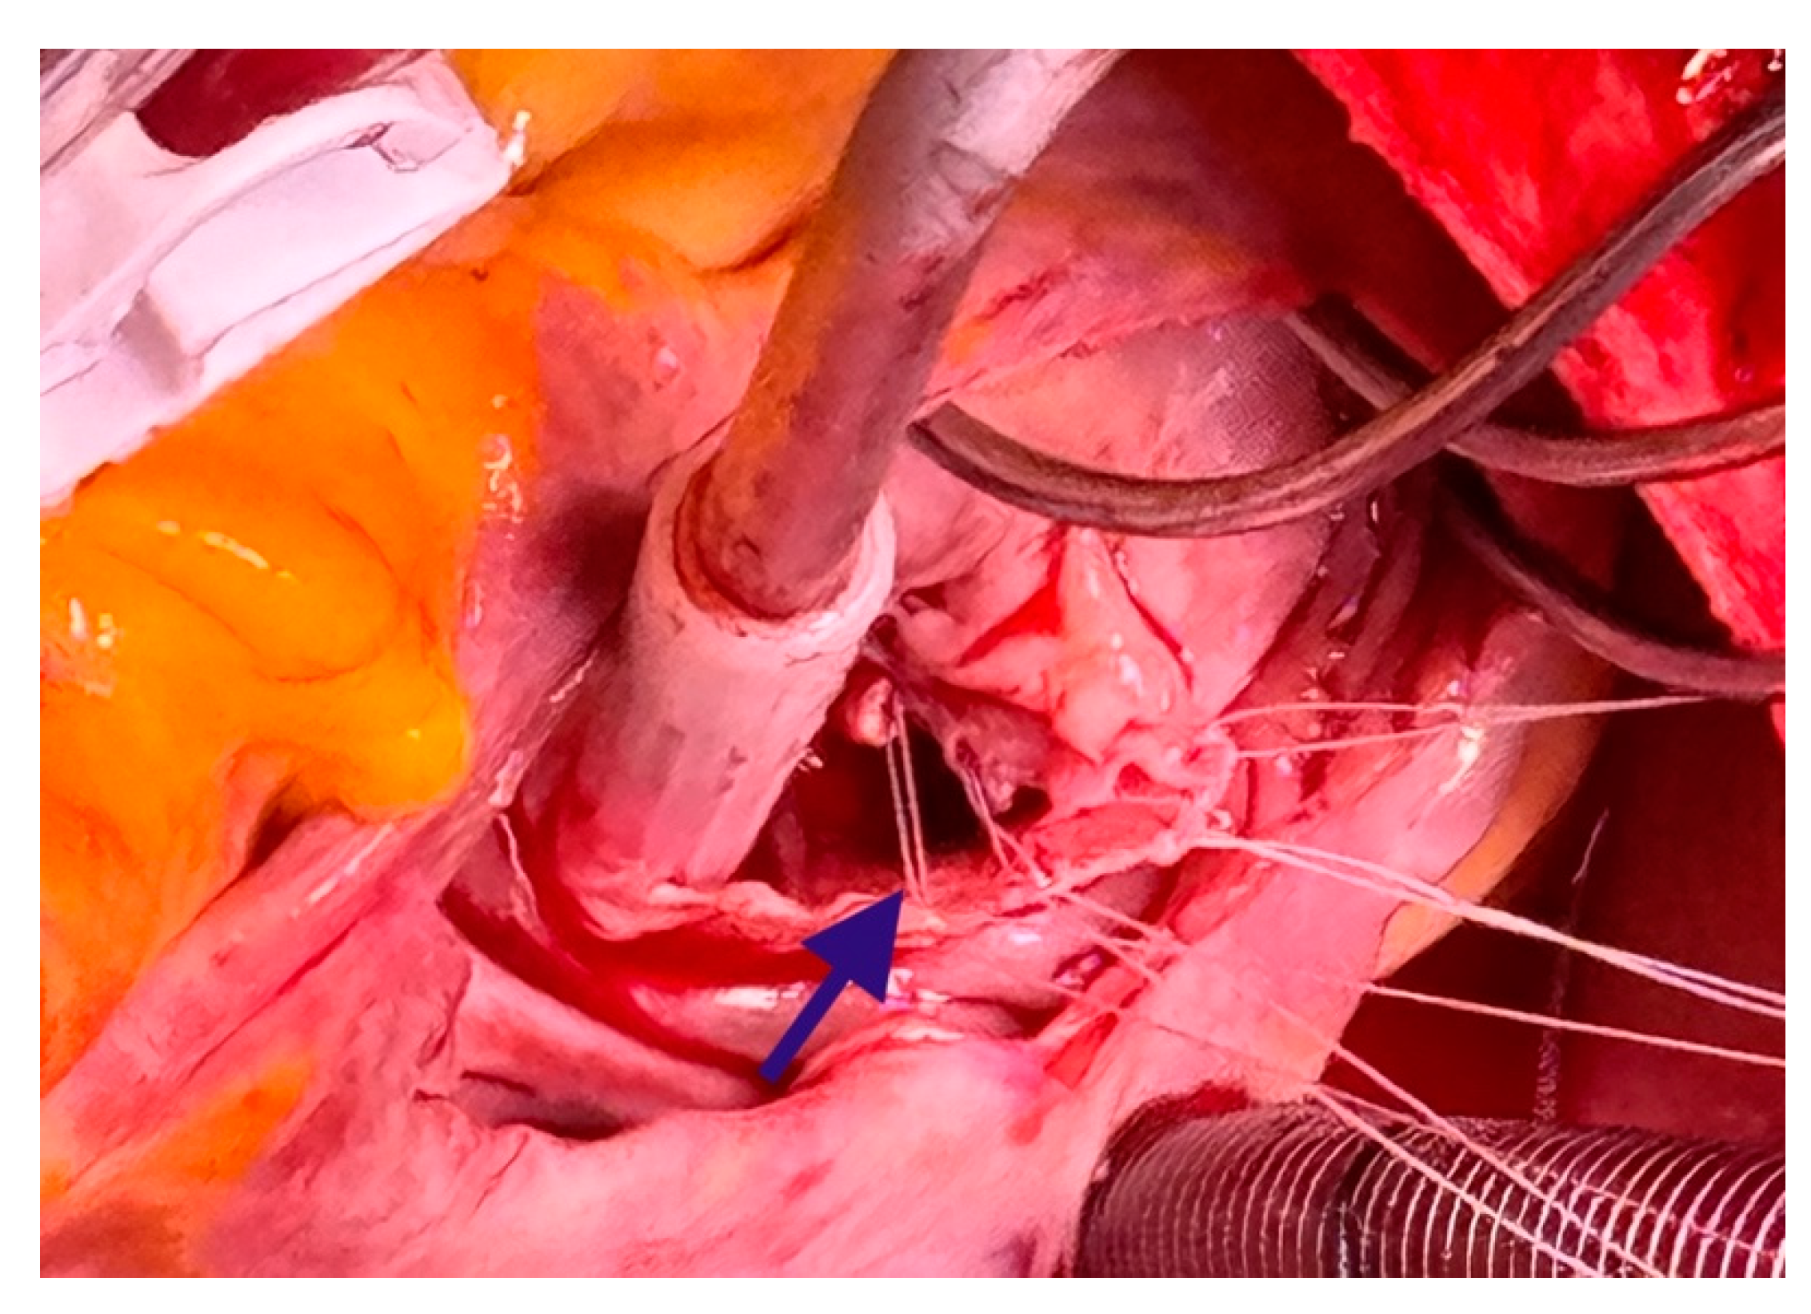

To achieve complete myxoma removal, the posterior leaflet chord was severed. Following the removal of the myxoma, the tip of the papillary muscle was resected. The tricuspid valve remained intact but exhibited insufficiency. The practitioners then decided to proceed with annuloplasty using a 30 mm Contour 3D annuloplasty ring (Medtronic, MN, USA). Subsequently, placement of 18 mm artificial chords (Seramon loops, Serag Wiessner, Naila, Germany) onto the posterior papillary muscle was carried out. The artificial chord was placed on the remnant non-fibrous part of the papillary muscle and two full-thickness bites were taken with pledgeted sutures. These four loops were then secured on the posterior and septal leaflets (Figure 5). The intraoperative echocardiography demonstrated valvular competence (Figure 6). The total duration of the operation was 198 min, with 70 min aortic of cross-clamping. During the procedure, the patient remained hemodynamically stable and was supported with 0.003 gamma noradrenaline. The patient was successfully extubated on the following day.

Figure 5. Placement of 18 mm Seramon loops (the blue arrow) onto the posterior papillary muscle.